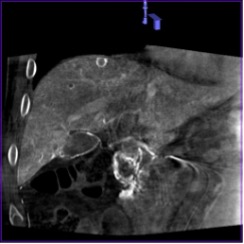

Высокое пространственное разрешение является ключевой сильной стороной ПДКТ, благодаря которой достигается четкая визуализация сосудов диаметром 250–300 мкм (0,25-0,30 мм) при проведении ПДКТ-артериографии (рис. 1). Такое высокое разрешение ПДКТ позволяет осуществлять прецизионный 3D-контроль установки стентов, микрокатетеров, тонких пункционных игл и других устройств непосредственно в рентгеноперационной (рис. 2). Пространственное разрешение характеризует точность воспроизведения малых структур в изоцентре и зависит от ряда факторов, таких как шаг пикселя, площадь сцинтиллятора, размер фокального пятна, геометрическое увеличение, стабильность системы во время сканирования, а также используемых фильтров реконструкции. Как уже было отмечено, применяемые в настоящее время a-Si:H/CsI:Tl ПДКТ-детекторы имеют высокие частотно-контрастные характеристики, благодаря конусовидному направлению света к каждому фотодиоду. Более толстый слой CsI улучшает поглощение, но увеличивает боковое размытие, снижающее контрастность, поэтому толщина и размер пикселя оптимизируются совместно [3, 4]. Пространственное разрешение напрямую зависит от режима считывания данных: при объединении (биннинге) пикселей, направленном на снижение шума и повышение контрастности получаемых изображений, пространственное разрешение прогрессивно снижается [35]. Как было показано в исследованиях на фантомах, ангиографическая установка Artis zee (Siemens Healthineers, Германия) при функции передачи модуляции (modulation transfer functions, MTF) в 10% достигает пространственного разрешения в 3,0 lp/mm при нативном считывании (1×1) и 1,5 lp/mm при биннинге 2×2, что превосходит разрешающую способность МСКТ (1,2–1,4 lp/mm в режимах высокого разрешения) [1, 35]. При использовании всех пикселей без их объединения разрешение может достигать почти 4,0 lp/mm, что соответствует возможности распознавания высококонтрастных деталей толщиной 130 мкм (0,13 мм) [35]. Переход на биннинг 2×2 удваивает размер эффективного пикселя с 154 мкм до 308 мкм, снижая MTF 10% вдвое, но повышая кадровую частоту до 30 кадров в секунду и минимизируя шум. При биннинге 4×4 (размер эффективного пикселя 616 мкм) разрешение падает до 1,0 lp/mm, однако возросшая скорость съёмки (60 кадров в секунду) и большее число проекций сокращает артефакты движения и улучшает контрастное разрешение, что чаще всего используется при визуализации органов брюшной полости и малого таза [35].

Рис. 1 (а-г). Церебральная ПДКТ-артериография бассейна правой общей сонной артерии, демонстрирующая возможность визуализации артерий диаметром 0,5 мм

Рис. 1а. Реконструкция всего артериального русла после проведения ПДКТ в режиме 20sDCT Head (Siemens Healthineers, Германия) с введением 60 мл контрастного препарата со скоростью 2 мл/с (в течение 30 с) и задержкой сканирования 10 с

Рис. 1б. Визуализация правой центральной артерии сетчатки глаза диаметром 0,5 мм в режиме MIP (тонкие срезы) у того же пациента

Рис. 1в-г. Визуализация той же артерии и дренирующих вен в косых проекциях (MIP) с использованием более толстых срезов.